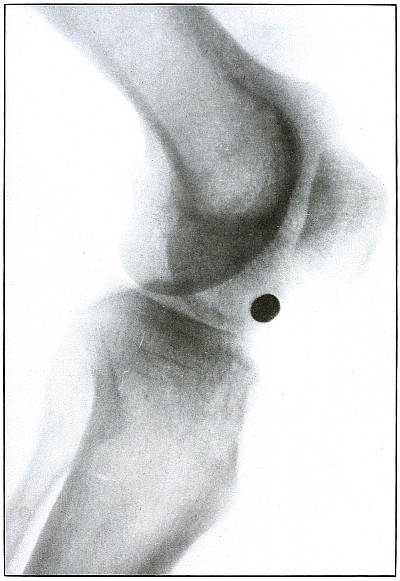

| 128.[Pg 6] |

Gunshot wound, knee |

266 |

| 129. |

Gunshot wound, knee |

268 |